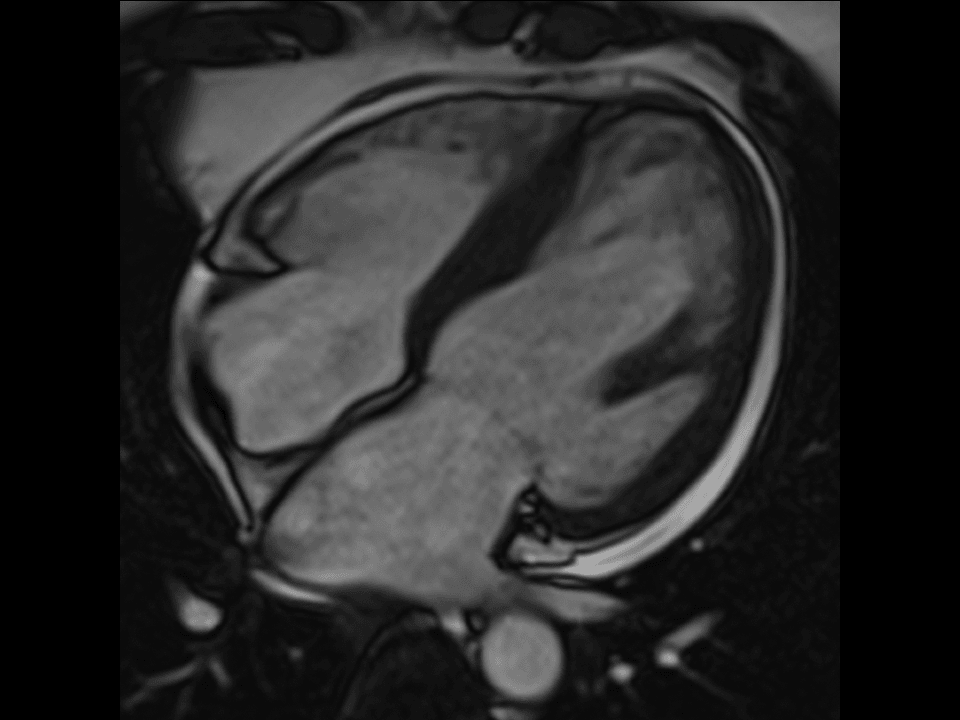

Experience excellent cardiac imaging capabilities and benefit from the high gradient power and Tim parallel imaging performance.